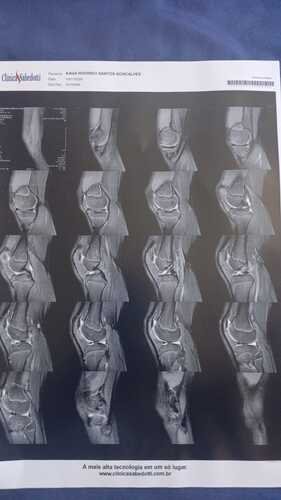

Eu sou Emanuelly, criei essa vakinha para conseguir juntar o valor total ou parcial de um procedimento cirúrgico chamado Artroscopia no joelho direito do meu irmão mais novo, ele sofreu um acidente no colégio Monteiro Lobato onde é aluno e estuda, infelizmente atualmente ele não consegue andar, a perna dele está perdendo massa muscular e perdeu os movimentos, ele está fazendo fisioterapia mas precisa urgentemente da cirurgia pra não ficar com sequelas, e não acabar atrofiando a perna direita dele.